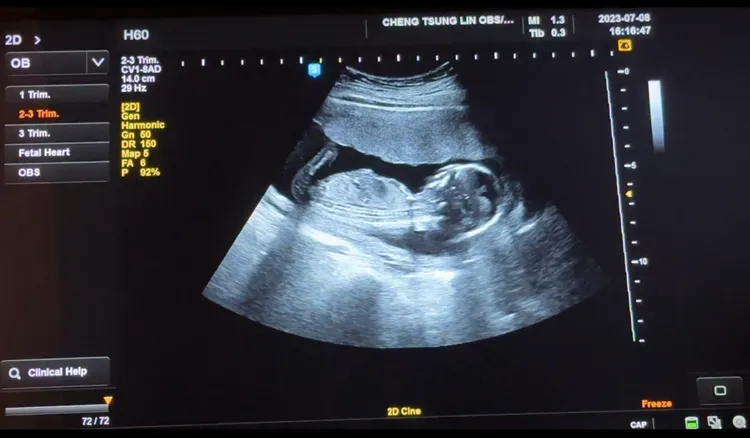

由於第一次懷孕時,樓心潼沒等3個月就分享喜訊,碰上胎停難免讓她有了顧忌,這次才會直到4個月穩定後才宣布,一併連秘婚的事也公開,她跟白家綺一樣都熬過了初期嚴重害喜時期,至於貝比性別,則打算屆時辦個性別派對。

後來樓心潼是在陳美鳳介紹下去找醫師做了2次試管,但失敗收場,黃鐙輝替她看紫微命盤子女宮,要她「別強求,順其自然」。她接下來跟方馨、白家綺等好姊妹去日本旅遊,期間還喝清酒玩得開心,沒想到回台灣後月經沒來,就在老公想帶她一塊去美國出差時,驗孕棒出現淡淡第2條線,可以想見夫妻有多開心。樓心潼到醫院檢驗已經懷孕7周,這次終於如願聽到寶寶健康有勁的心跳聲了。